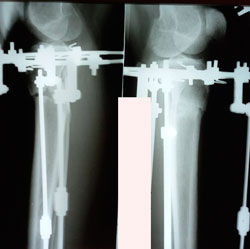

Исходник - 29 лет.

Дата операции - 29.09.2020

Мальчик